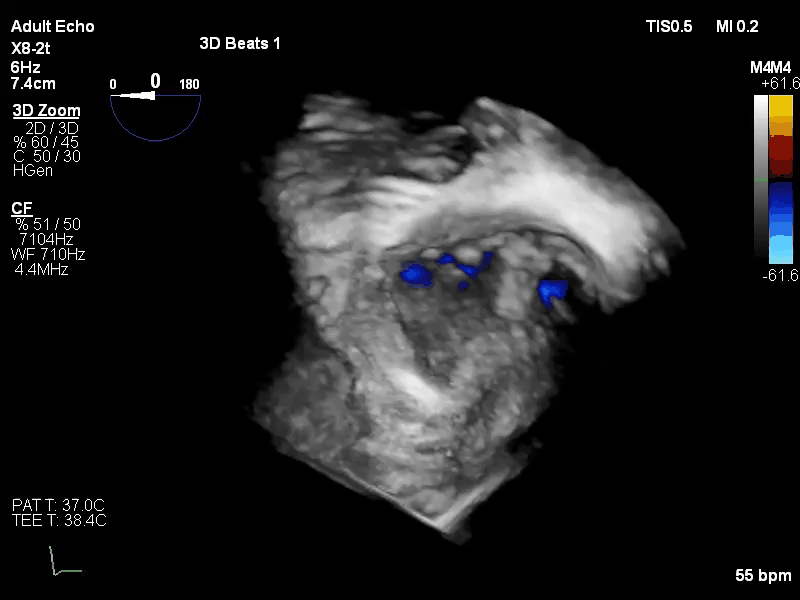

病例三

术前评估:

Carpentier II,DMR,二尖瓣P2区域腱索断裂导致极重度二尖瓣反流,心脏扩大,瓣口面积12cm²。反流束来自于2区,呈偏心性,沿前叶走行,EROA=0.51cm²,VC 0.97cm。

手术于全麻下进行,采用股静脉房间隔途径,房间隔穿刺后置入外径22F导管鞘及夹合器输送系统,在TEE引导下,将1枚长宽型号的KoKaClip®夹合器顺利植入到二尖瓣2区,夹合器位置稳定。彩色多普勒超声未见明显残余反流,肺静脉多普勒波形由反向恢复正常。多切面证实夹合组织充分,双孔化形成,遂移除器械输送系统,移除后夹合器活动度小,手术顺利完成,患者已于近日出院,出院超声复查良好。

术前

术后